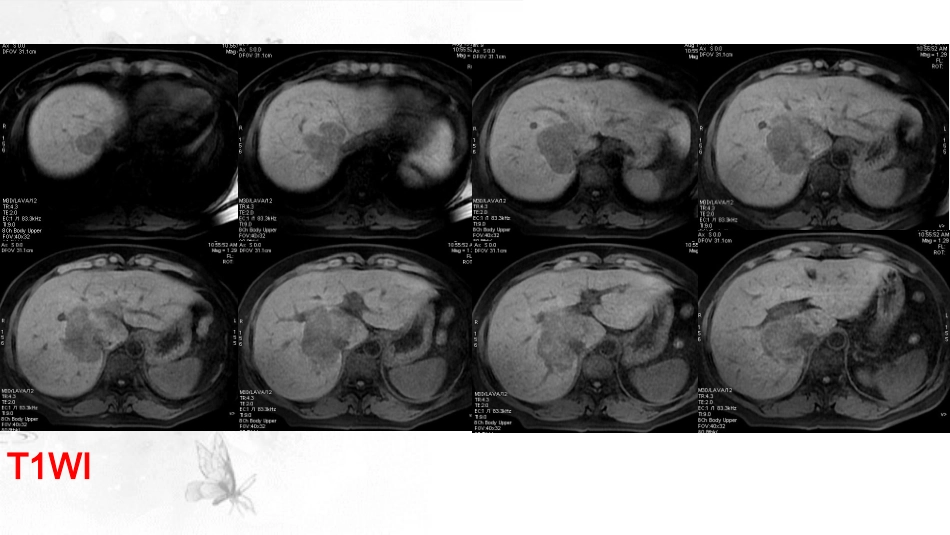

病例讨论漯河医专二附院·孙英杰病史摘要:女,49岁,上腹不适月余;超声发现肝内占位。T1WIT2WIDWIT2WI动脉期平衡期延迟期延迟期T2DWI动脉期平衡期延迟期T1病理结果提示:肝内胆管细胞癌胆管细胞癌胆管细胞癌是胆管上皮发生的恶性肿瘤,可发生于胆管系统任何部位,是常见的原发性肝癌之一;其中腺癌为绝大多数,约90%以上。50岁以上的男性为高发群体;该疾病发病机制尚不完全明确.但研究认为和结石、慢性感染、胆管分支异常等具有密切联系。胆管细胞癌按部位分型:1、周围型胆管细胞癌:也称肝内型胆管细胞癌,定义为在肝内二级分支胆管以上末梢部位,约占20%~25%。2、肝门型胆管细胞癌:在肝内二级分支胆管与肝总管末端之间发生的肿瘤,约占50%~60%。3、肝外胆管型胆管细胞癌:胆总管发生的肿瘤称为远端胆管细胞癌,约占20%~25%。日本肝癌研究组(LCSGJ)依据胆管细胞癌的生长方式将其分为肿块/结节型、腔内生长型及浸润型,其中在肝内型胆管细胞癌中肿块/结节型是最常见的类型,浸润型则是肝门部胆管细胞癌的最常见类型。胆管细胞癌的组织学分型:胆管细胞癌95%以上为腺癌,其中高分化腺癌最常见,约占60%~70%,中分化腺癌约占15%~20%,低分化及未分化型少见。其它少见组织学类型还有腺鳞癌、粘液癌、鳞癌、印戒细胞癌等。胆管细胞癌病理学特点肝内胆管细胞癌·病理特点肝内胆管细胞癌一般较大,内部纤维基质含量多,外部形态表现为灰自色实质鱼肉样。肿瘤内大量的纤维间质,以中央区分布最丰富,成活的肿瘤细胞则主要分布于肿瘤的外带,中心区则分布较少。淋巴结转移多见。肝内胆管细胞癌CT影像学特征:·多数肝门部胆管走行区可见不规则低密度肿块;可伴随肝叶萎缩。·可伴有远端肝内胆管扩张,可见“枯枝状”或“软藤状”改变。·增强扫描:典型的肿瘤瘤体动脉期周边呈现环状、斑片状强化,于延迟期会向中央进展,在内部纤维组织的影响,延迟增强时间较长。一部分肿瘤动脉期肿瘤也可无明显强化,门脉期及静脉期则多可见到不同程度的强化,延迟期病灶多呈持续强化。·可有门脉癌栓及淋巴结转移。肝内胆管细胞癌MRI影像学特征:·肝内胆管系统的不规则形肿块影,TIWI上多呈较均匀稍低或等信号,T2WI上多数呈不均匀稍高信号;胆管细胞癌病灶在DWI图上呈高信号,ADC图上呈低信号。·可伴有不同程度的胆管扩张,可见“枯枝状”或“软藤状”改变。·增强扫描:同CT。·可有门脉癌栓及淋巴结转移。肝内胆管细胞癌增强扫描:动脉期:早期环状强化的病理基础是肿瘤周边恶性肿瘤细胞占多数。肝内型胆管细胞癌病灶周围可呈小片状强化,这是由于肿瘤组织对门静脉分支直接浸润,或肿瘤组织对邻近的门静脉产生压迫,使肝动脉和门静脉系统之间发生异常沟通所致。延迟强化:的病理基础是肿瘤中心部位含有大量纤维组织,虽然造影剂进入纤维组织中相对缓慢,但在其中存留时间较长,这是肝内型胆管细胞癌延迟强化的病理基础。肝内胆管细胞癌增强扫描:肝内型胆管细胞癌增强病灶可不强化、周边出现环形强化、均匀强化或条片状强化等多种表现,这种表现与肿瘤内部肿瘤细胞和纤维基质的含量不同等有关;肿瘤可以浸润门静脉。肝动脉期和门静脉期病灶边缘出现菲薄、轻度的不连续环形强化是最常见的CT增强表现,以后向中心区逐渐强化,形成典型的延期强化。肝内胆管细胞癌研究显示:动脉期富血供组肿块的强化程度高于乏血供组,这是由于富血供组肿块的强化区域内富含胆管细胞,且肿瘤细胞比例较高,而中央纤维基质和坏死成分较少。但有研究显示:乏血供肿块型胆管细胞癌随着恶性肿瘤的生长,病理特征如坏死、纤维化和对邻近结构的侵犯效应较富血供肿块型胆管细胞癌发生早。同时有研究表明乏血供组5年生存率较富血供组低。MRI影像学其他特征:肝叶/段萎缩、包膜内陷、周围胆管扩张对诊断胆管癌也有特异性。肝内型胆管细胞癌检查时常可发现胆管结石。肝内胆管细胞癌钙化远端胆管扩张肝叶萎缩胆管细胞癌肝门部结构不清,平扫病灶呈稍低密度影;动态增强动脉期病灶周边环状及及条状强化,延迟期强化持续性存在,伴肝内胆管扩张;肝内多发转移灶。胆管细胞癌胆管细胞癌动脉期门脉期平衡期平扫胆管细胞癌动脉...